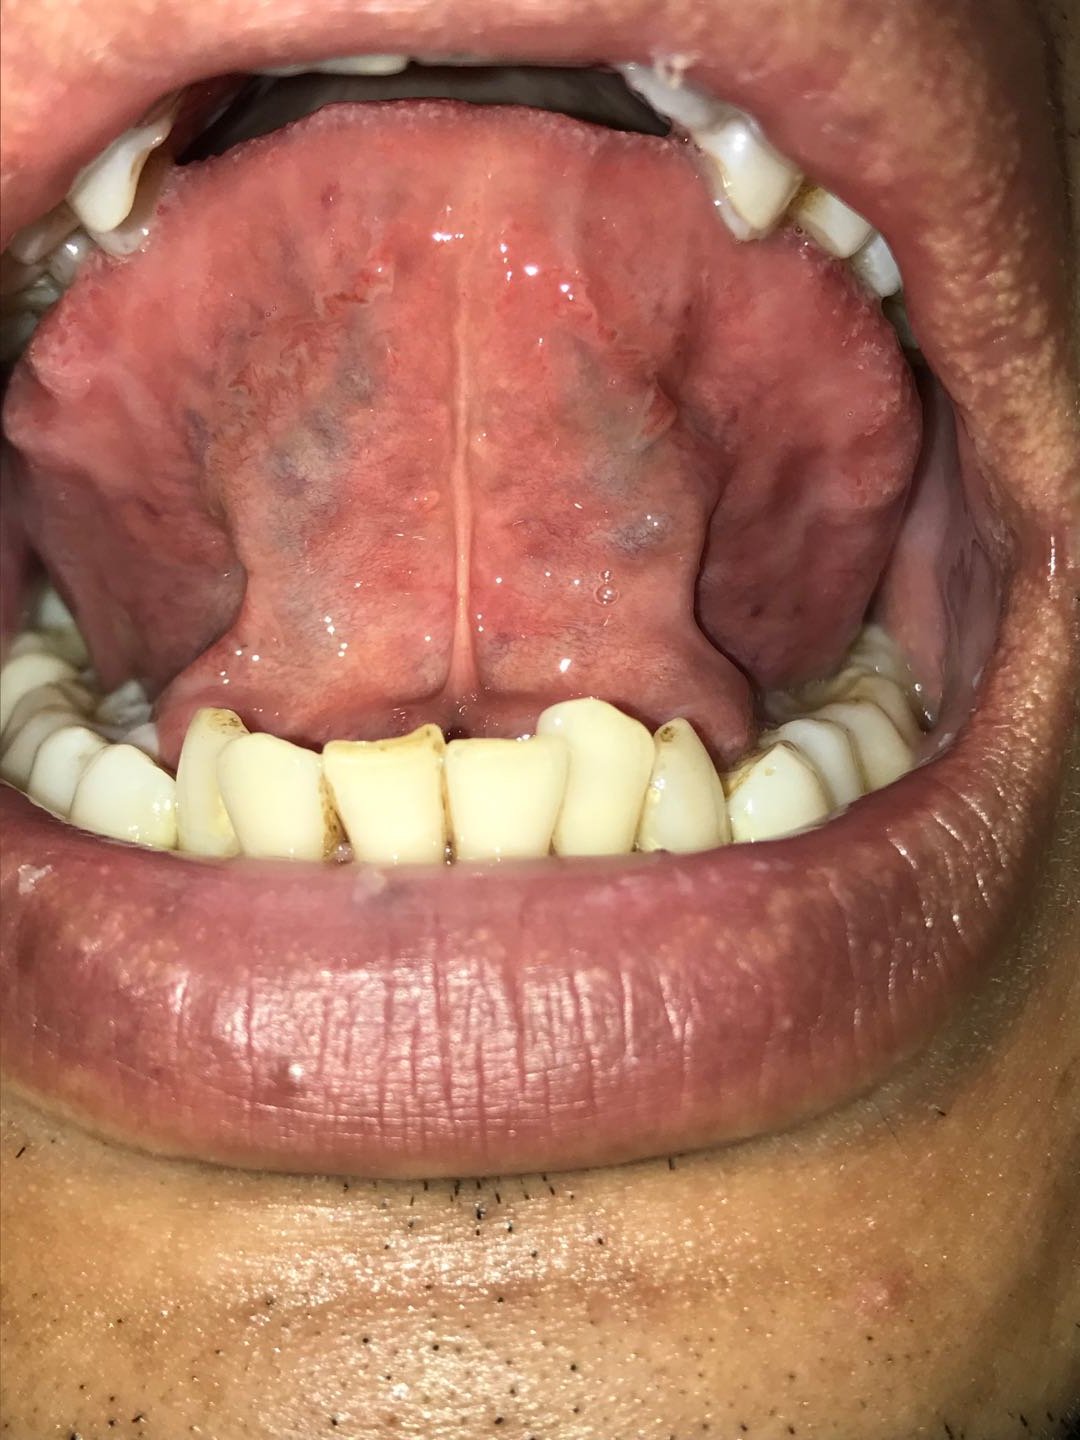

1、舌苔黄厚,如下图所示;